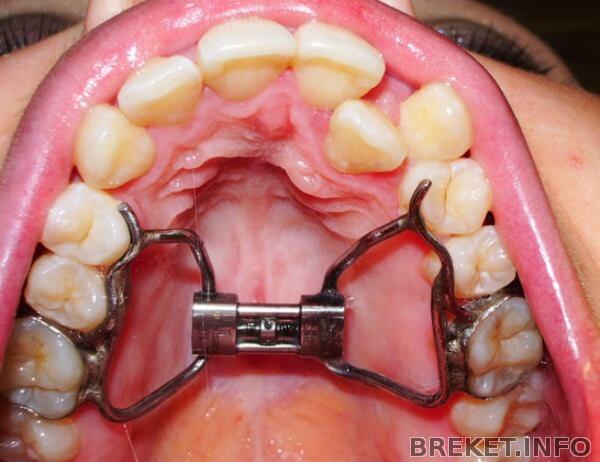

Мне 33 года. Ортодонт говорит, что верхняя челюсть с одной стороны узкая, и нужно устанавливать аппарат дерихсвайлера. Я читала, что его нужно ставить до 23 лет, и вообще у пациентов постарше могут быть плохие последствия.... Еще начиталась, насмотрелась на этот ужас в интернете, и поняла, что 100% ставить его не хочу, не буду, и не могу... Языку и без него сейчас мало места, еще рвотный рефлекс, плюс ужасная паника что во рту что-то есть чего не могу выплюнуть - я себя знаю(((( Вот ничего не могу с собой поделать(((

Стоит вот такой

Попробуйте ещё проконсультироваться. На этот счёт есть разные взгляды и подходы. Но использование таких штук у взрослых без применения хирургии довольно рисковано. Насколько я понимаю, дело в высоком давлении, которое этот аппарат оказывает на зубы и альвеолярный отросток. Если есть возможность, лучше поправить брекетами, они действуют мягче. В любом случае сама челюсть уже не растет, а значит все эти танцы с бубном исключительно за счёт некоторого преобразования зубного ряда. У меня как раз расширение на брекетах идёт. Но некоторые врачи пользуются такими аппаратами. Так что тут дело в вашем доверии. Если доверяете мнению ортодонта, то делайте как он предлагает. Привыкнуть можно по всему.